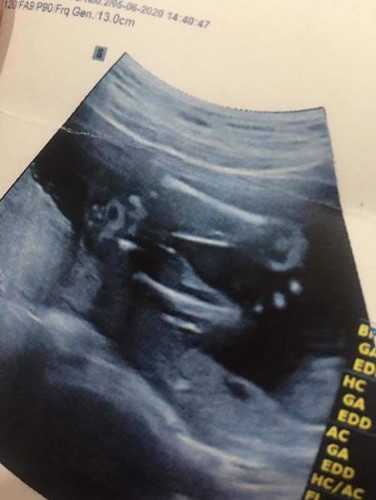

ผู้หญิงหรือผู้ชายค่ะแม่ๆ

ลูกสาวตามหมอบอกค่ะแม่ ถ้าลูกชายจู๋จะโผล่ชัดกว่านี้ค่ะ

น่าจะผู้หญิงนะคะเพราะตรงหว่างขาไม่มีจู๋ค่ะ

ผญ.ค่ะ ถ้าผช. จู๋จะชี้มาแบบนี้เลยค่ะ 😆

ญ ค่ะ เพราะตรงหว่างขา ไม่มีจู๋ค่า 😆

ผ.ญค่ะ ไม่มีกะจู๋

เหมือนจะ ผญ นะคะ